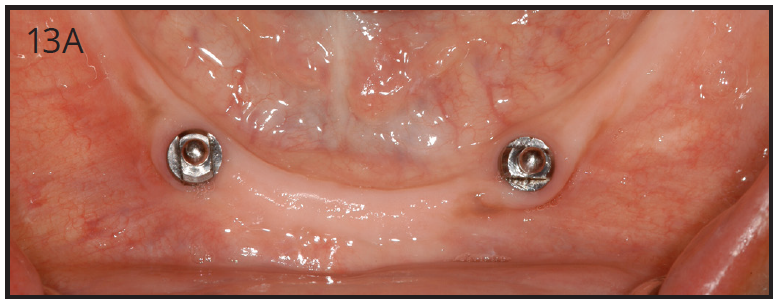

As stated earlier, dentures replace only about 10% of chewing function. This causes digestive problems, due to an inability to chew food properly, also leading to malnutrition, due to an increase in consumption of softer, more processed foods. This inability to chew also results in atrophy of the alveolar arches due to lack of adequate pressure on the bone. When the denture is pressing on the mental foramen, then patients will experience pain and numbness of the lower lip. A good solution for these denture wearers is to place 2 to 4 implants in the mandible to stabilize the denture. The denture is then attached to the implants via snap-on attachments or a bar. (Figures 13A-C) According to the 2002 McGill Consensus Statement on Overdentures, mandibular two-implant overdentures are superior to conventional dentures in all clinical trials, even up to nine years in function.32

Figure 13A – Mandibular, two-implants with O-rings to support the overdenture

Figure 13A